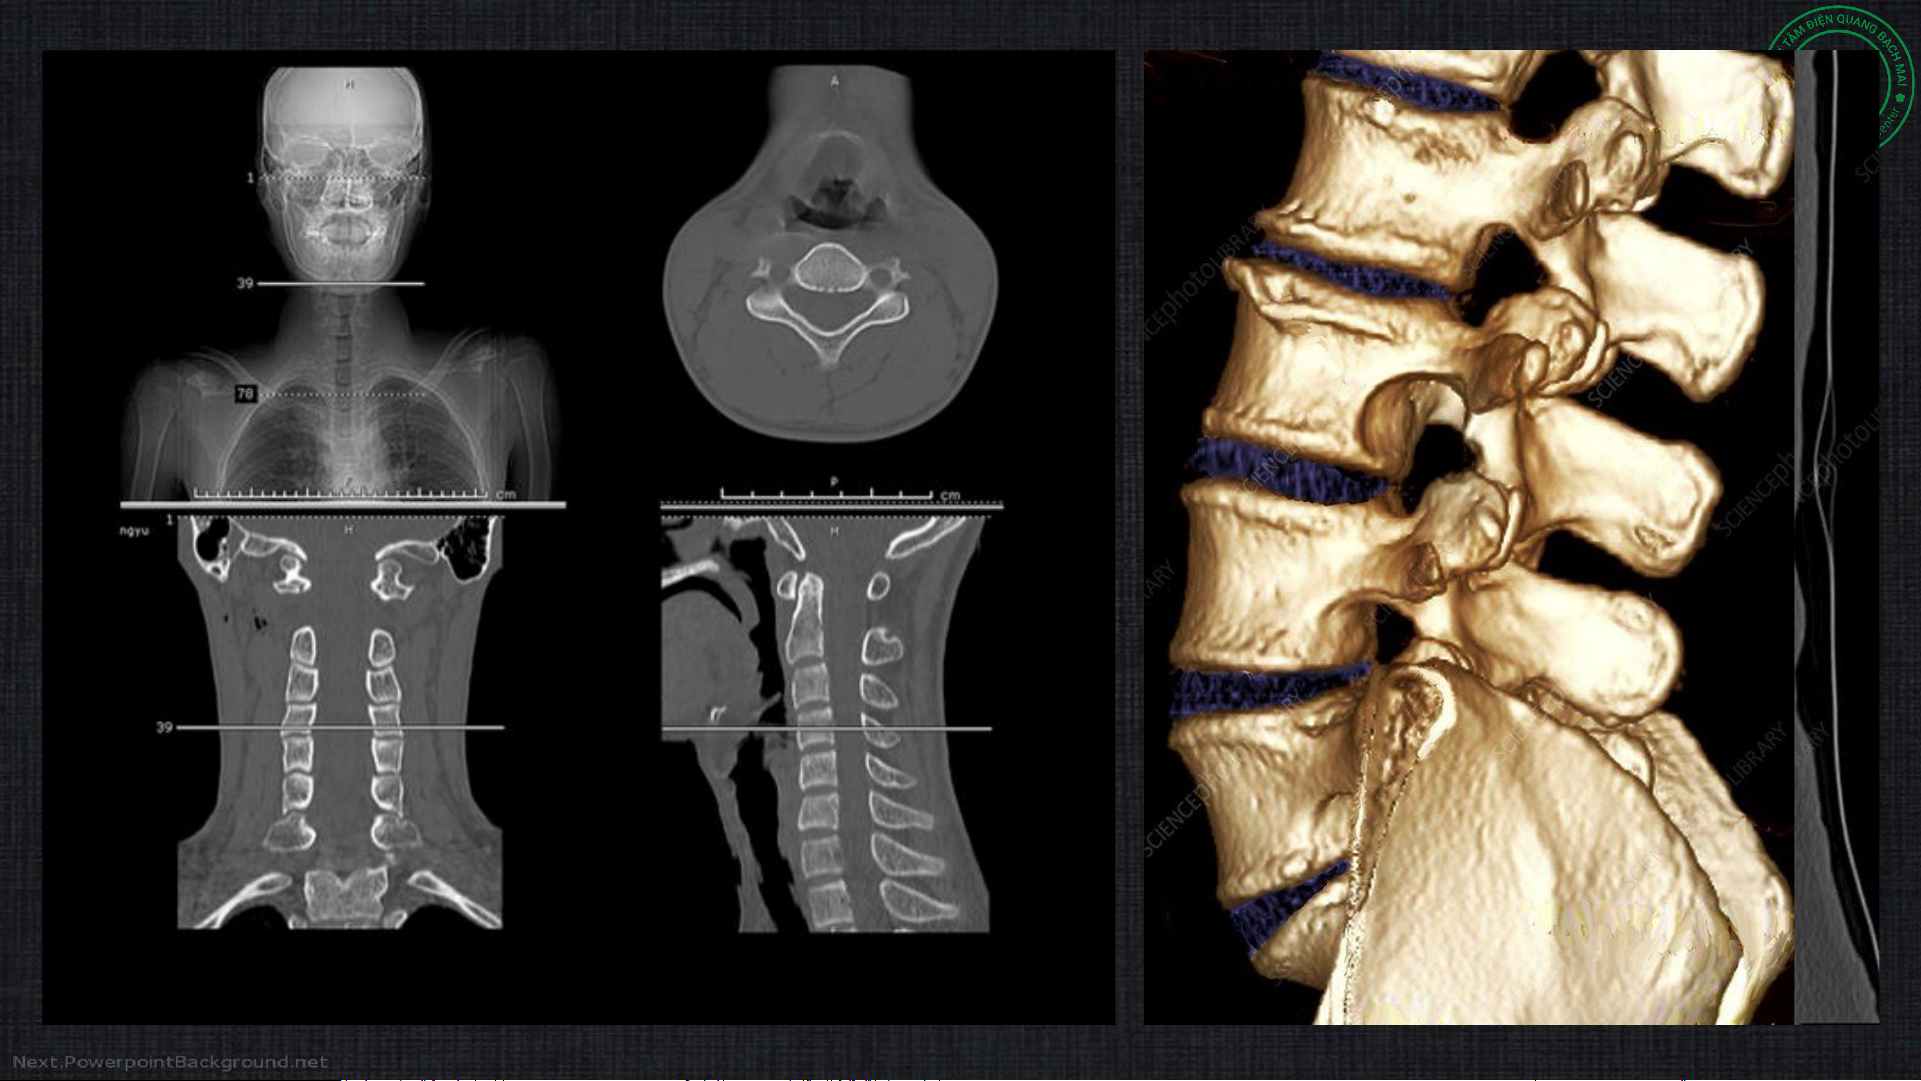

2b. Chụp cắt lớp vi tính • Sử dụng tia X

• Dựng hình đa mặt phẳng (axil, coronal, sagittal)

• Có thể đánh giá tổ chức phần mềm tốt hơn Xquang (đo tỷ trọng)

• Cửa sổ xương và phần mềm

• Đánh giá cột sống và cấu trúc xương tốt hơn

• Độ phân giải không gian kém/ nhiễu ảnh do xương → hạn chế đánh giá tủy

sống, phần mềm so với cộng hưởng từ

• Ít xâm lấn, có thể chụp cùng thuốc cản quang trong tủy sống (myelography) Cửa sổ xương Cửa sổ phần mềm Tụ máu NMC Nhiễu ảnh